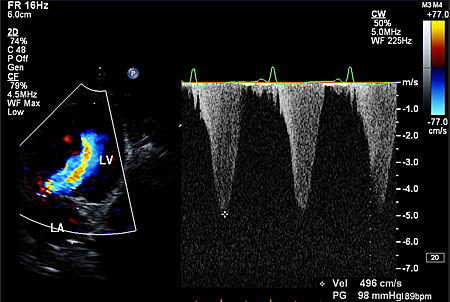

閉塞性肥大型心筋症

心筋肥大があり、僧帽弁前尖や腱索の収縮期前方運動により左室流出路が閉塞し、収縮後期加速(ダガーシェイプ)が認められる場合に閉塞性肥大型心筋症と診断します。

重度の動的左室流出路閉塞を伴う閉塞性肥大型心筋症の大動脈血流速波形

収縮後期加速(ダガーシェイプ)が認められ、最高血流速度は4.96 m/秒